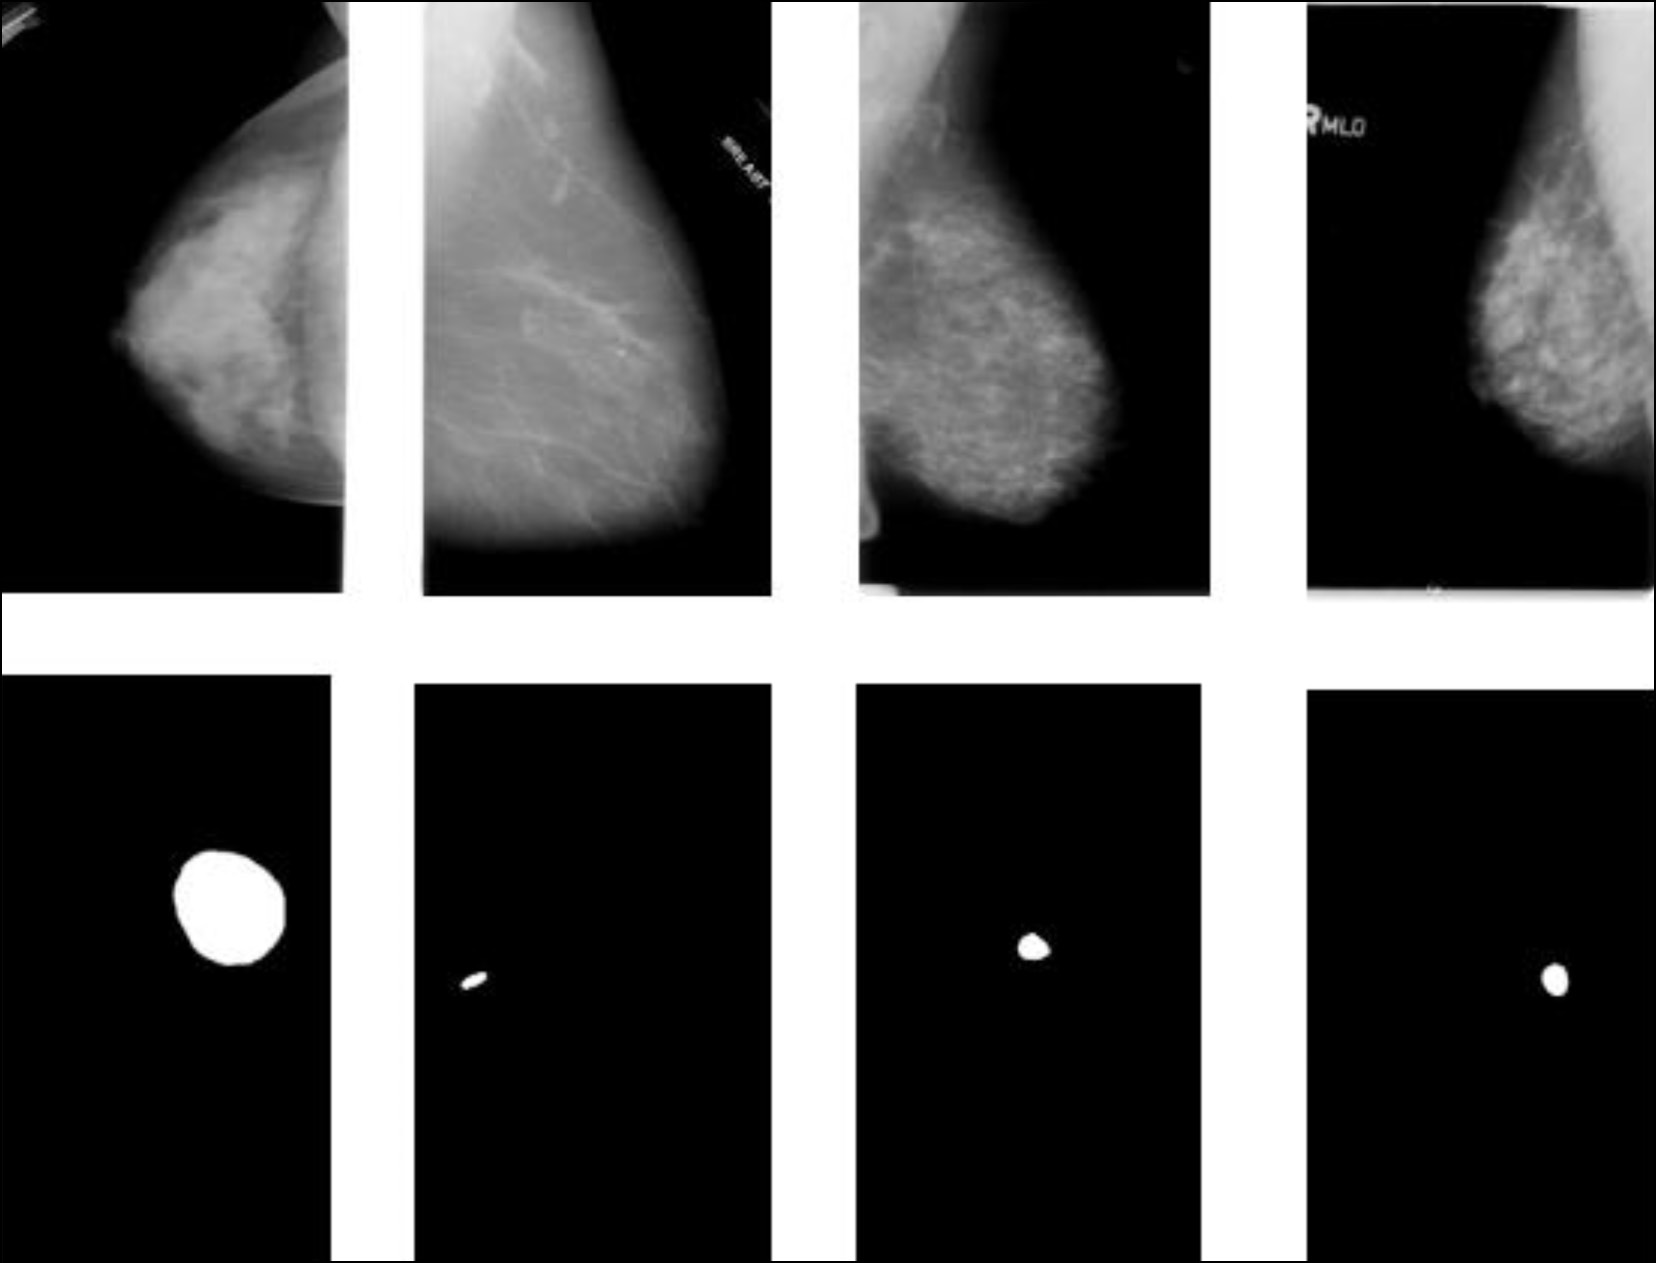

利用机器学习方法诊断乳腺癌

最近几年,机器学习方法在诊断领域,特别是对乳腺癌的检测受到越来越多的关注。

文章从三个方面分析了当前致力于在乳腺癌诊断中使用机器学习方法的研究:用于解决现代乳腺癌诊断中出现的辅助任务,作为初步诊断决策的患者病情智能评估,以及确定乳腺癌的风险因素。文章从三个方面分析了机器学习方法在乳腺癌诊断中的应用现状:解决现代乳腺癌诊断中出现的辅助课题,智能评估患者病情初步诊断决策,以及确定乳腺癌的风险因素。

分析表明,利用机器学习方法诊断乳腺癌为提高诊断的准确性和效率提供巨大的可能性,并且还可以完成其他额外任务。

文献分析结果,确定了用作机器学习方法中输入数据的特征。今后,收集到的信息将用于构建一个利用机器学习方法诊断乳腺癌的特征系统。

本文描述了一个罕见的继发性乳腺血管肉瘤病例,患者是一名72岁的女性,患者是一名有乳腺癌病史的 72 岁女性。曾患乳腺癌。患者因左乳房外上象限无痛性可触及硬块来我院就诊,接受了全面的诊断检查,包括乳腺科、病理科和肿瘤科的会诊。在乳房造影、超声检查和磁共振成像等仪器诊断方法的帮助下,成功评估肿瘤的扩散程度、淋巴结损伤情况,以及是否存在远处转移。 组织活检结果证实了诊断。本文分析这一罕见病例的主要目的是教育性的,包括描述该疾病的临床表现和复杂诊断,以及讨论鉴别诊断和治疗策略。继发性乳腺血管肉瘤是一种罕见的侵袭性肿瘤,了解其独特之处对于做出正确的临床决策和改善患者的预后至关重要。由于发现较晚、硬块远处转移的风险增加以及治疗方案有限,该肿瘤的预后较差。在这种情况下,需要密切监测、采取积极的治疗策略和姑息治疗。